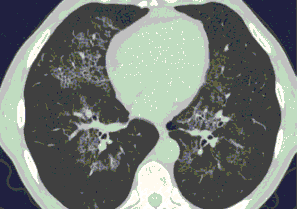

Методы лучевой диагностики применяют для выявления COVID-19 пневмоний, их осложнений, дифференциальной диагностики с другими заболеваниями легких, а также для определения степени выраженности и динамики изменений, оценки эффективности проводимой терапии.

К методам лучевой диагностики патологии ОГК пациентов с предполагаемой/установленной COVID-19 пневмонией относят:

- Компьютерную томографию легких (КТ),

Стандартная РГ имеет низкую чувствительность в выявлении начальных изменений в первые дни заболевания и не может применяться для ранней диагностики. Информативность РГ повышается с увеличением длительности течения пневмонии. Рентгенография с использованием передвижных (палатных) аппаратов является основным методом лучевой диагностики патологии ОГК в ОРИТ. Применение передвижного (палатного) аппарата оправдано и для проведения обычных РГ исследований в рентгеновском кабинете. В стационарных условиях относительным преимуществом РГ в сравнении с КТ являются большая пропускная способность. Метод позволяет уверенно выявлять тяжелые формы пневмоний и отек легких различной природы, которые требуют госпитализации, в том числе направления в ОРИТ.

КТ имеет высокую чувствительность в выявлении изменений в легких, характерных для COVID-19. Применение КТ целесообразно для первичной оценки состояния ОГК у пациентов с тяжелыми прогрессирующими формами заболевания, а также для дифференциальной диагностики выявленных изменений и оценки динамики процесса. КТ позволяет выявить характерные изменения в легких у пациентов с COVID-19 еще до появления положительных лабораторных тестов на инфекцию с помощью МАНК. В то же время, КТ выявляет изменения легких у значительного числа пациентов с бессимптомной и легкой формами заболевания, которым не требуется госпитализация. Результаты КТ в этих случаях не влияют на тактику лечения и прогноз заболевания при наличии лабораторного подтверждения COVID-19. Поэтому массовое применение КТ для скрининга асимптомных и легких форм болезни не рекомендуется. При первичном обращении пациента с подозрением на COVID-19 рекомендуется назначать КТ только при наличии клинических и инструментальных признаков дыхательной недостаточности (SpO2 < 95%, ЧДД > 22).

3. Применение лучевых методов у пациентов с симптомами ОРВИ легкой степени тяжести и стабильном состоянии пациента, возможно только по конкретным клиническим показаниям, в том числе при наличии факторов риска, при условии достаточных технических и организационных возможностей. Методом выбора в этом случае является КТ легких по стандартному протоколу без внутривенного контрастирования или РГ при ограниченной доступности КТ. Использование УЗИ в этих случаях нецелесообразно. Применение КТ исследования в сроки ранее 3 - 5 дней с момента появления симптомов заболевания, а также при отсутствии клинических проявлений поражения бронхолегочной системы является нецелесообразным. Выполнение КТ целесообразно при наличии клинических и инструментальных признаков дыхательной недостаточности (SpO2 < 95%, ЧДД > 22), либо при дифференциальной диагностике с другим заболеванием.